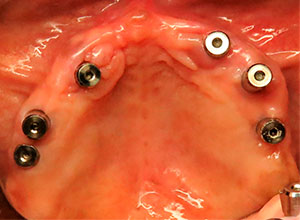

Fotografía post operatoria al més de la cirugía